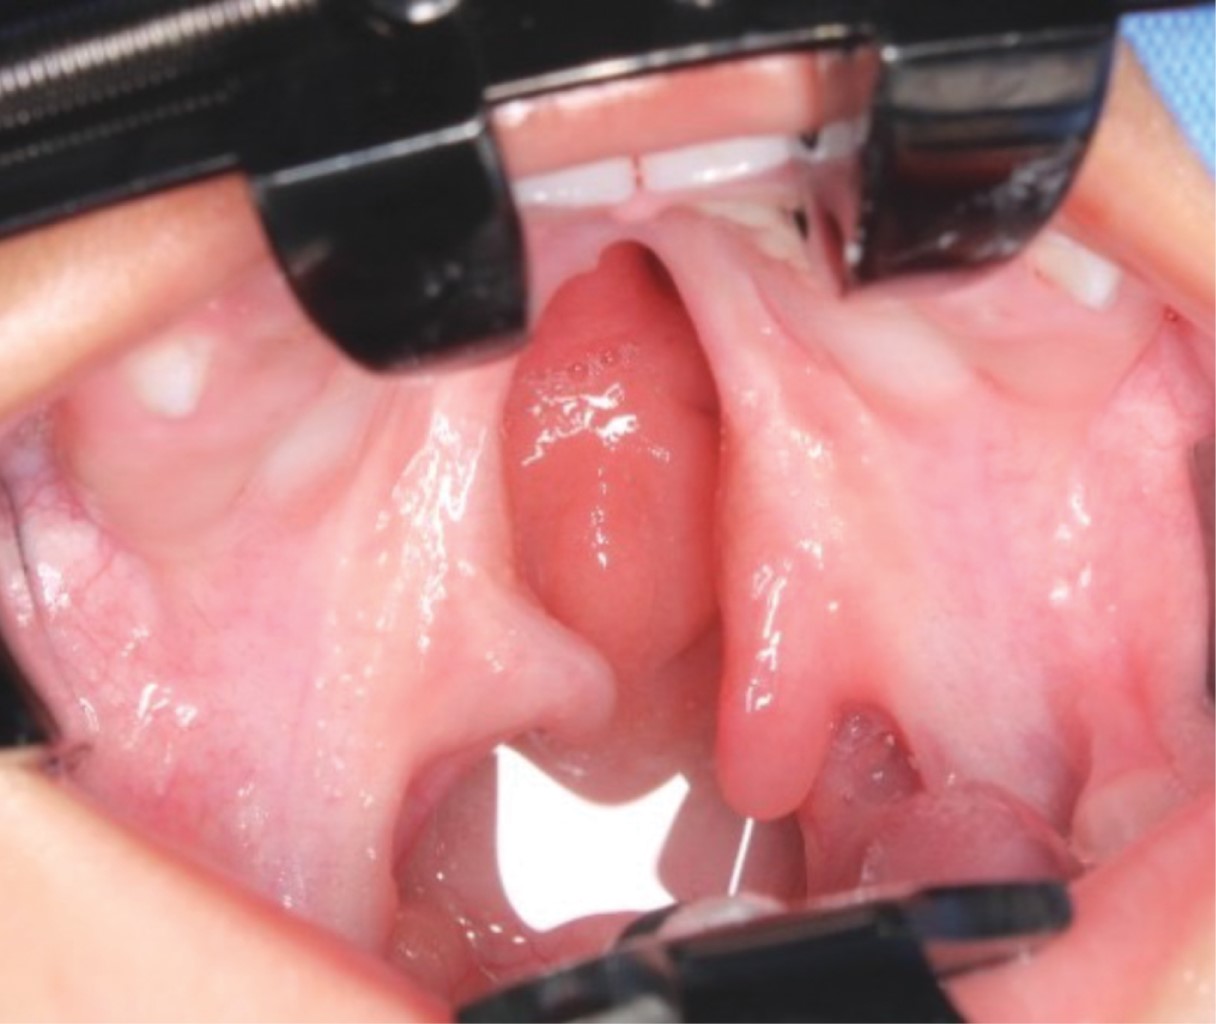

Se presenta el caso de un paciente pediátrico masculino, quien fue llevado al Servicio de Cirugía Maxilofacial del Centro de alta Especialidad "Dr. Rafael Lucio" a la edad de un año cinco meses. Fue valorado y diagnosticado con fisura de paladar secundario clasificación II de Veau (Figura 1), por lo que se le realizó palatoplastia mediante técnica de veloplastia intravelar bajo anestesia general balanceada; la cirugía se llevó a cabo sin complicaciones ni eventualidades (Figura 2). El paciente fue dado de alta; acudió a controles posquirúrgicos a la semana, al mes y a los seis meses; durante este seguimiento fue posible observar la presencia de una fístula palatina Pittsburgh IV +, Cohen II, la cual provocaba paso de líquidos desde la cavidad oral a la nasal (Figura 3).

Figura 1